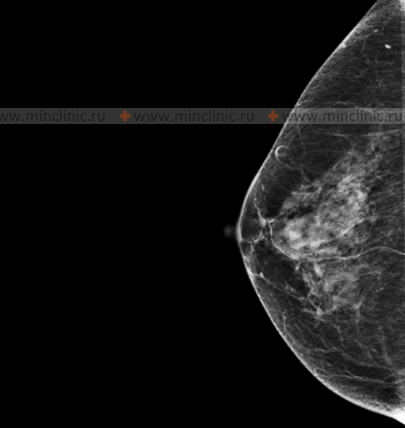

Diagnostic Methods: Mammography and Ultrasound

The main method for objectively assessing the condition of the mammary glands, particularly for screening, is X-ray examination, known as mammography. This imaging technique allows for the timely recognition of pathological changes in the mammary glands in a high percentage of cases (e.g., 95-97%). It is this quality, in contrast to some other diagnostic methods, that makes mammography the leading screening method for breast cancer. Approximately 80% of non-palpable neoplasms (cancers too small to be felt) in the mammary glands are detected during primary screening mammography.

Annual mammogram screening of the mammary glands is a crucial tool that can detect non-palpable (unable to be felt) Stage 1 breast cancer in a high percentage of women (e.g., historically cited as 93% in some cohorts), significantly improving prognosis.

The high diagnostic value of mammography and the use of modern equipment with minimum radiation doses make it possible to achieve a significant reduction in breast cancer mortality through early detection.

Ultrasound of the mammary glands is another important diagnostic tool. It is often used:

- As a supplementary examination to mammography, especially in women with dense breast tissue (where mammography may be less sensitive).

- To differentiate between cystic (fluid-filled) and solid masses found on mammography or clinical examination.

- As the primary imaging modality in younger women (e.g., under 30 or 35), pregnant or lactating women, due to the absence of ionizing radiation.

- To guide biopsy procedures (e.g., ultrasound-guided core needle biopsy).